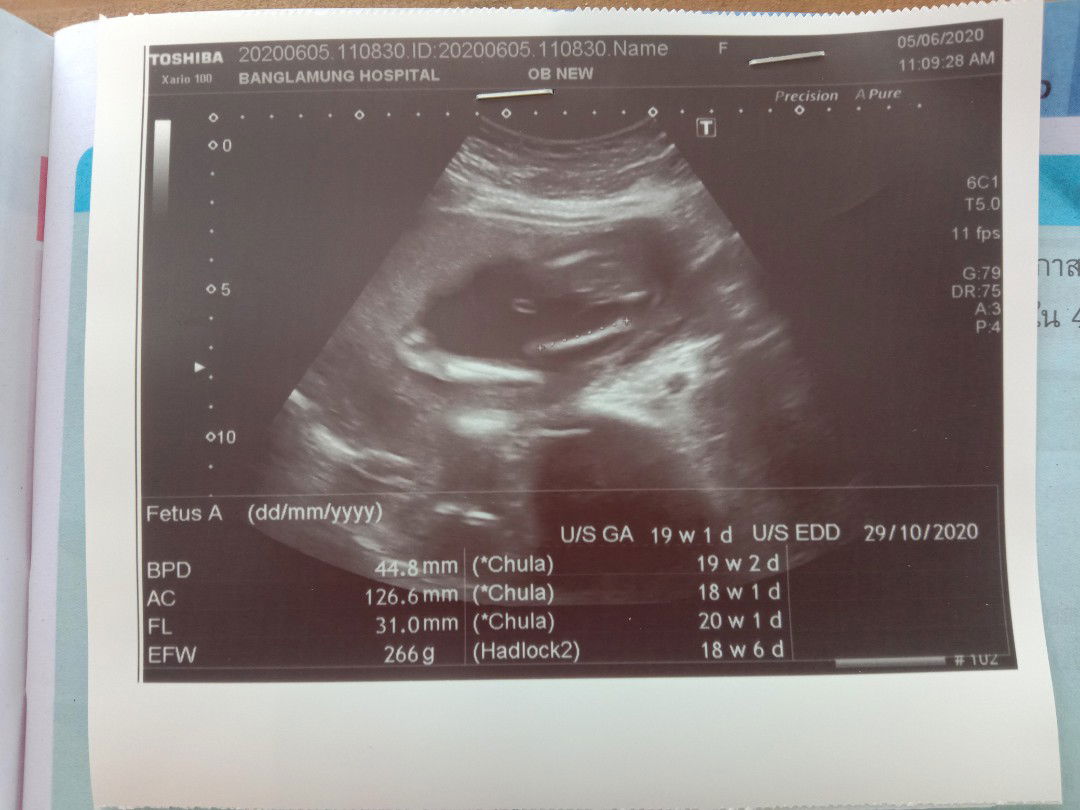

ดูลูกตรงไหนหรอคะ

ไปซาวด์ท้องมาวันนี้หมอไม่บอกอะไรเลยบอกแค่กำหนดคลอดซาวด์มาแค่นี้เราไม่รู้จริงๆว่าควรดูลูกยังไง

ทำไมหมอให้ไปซาวด์ตอน 18 วีคคะ

เราเห็นแม่บ้านอื่นไปซาวด์กันตั้งแต่ 13วีคบ้างล่ะ เราก็อยากเห็นหน้าตัวเล็กไวๆตอนนี้ 15 วีคแล้วค่ะ